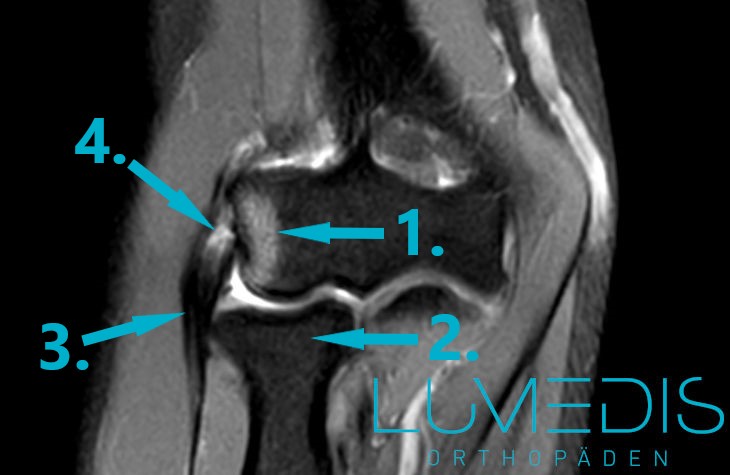

MRT eines schweren Tennisarms mit Sehnenanriss